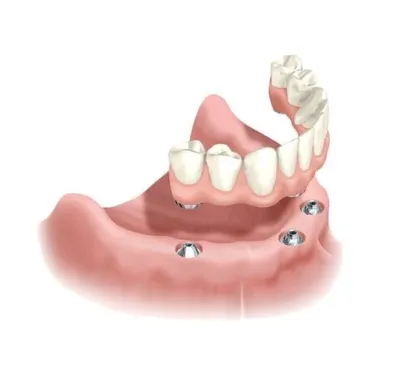

If you’re struggling with loose dentures or missing most or all of your teeth, the All-on-4 (also known as All-on-X) treatment concept offers a life-changing solution. This innovative approach allows us to replace an entire arch of teeth using as few as four strategically placed dental implants—providing a secure, natural-looking, and long-lasting alternative to removable dentures.

All-on-4 refers to a full arch restoration supported by four dental implants, while All-on-X allows for more than four implants (typically 4–6), based on your bone anatomy and clinical needs. These implants act as anchors for a custom-designed set of teeth that is securely fixed in place—no adhesives, no slipping, no daily removal.

On the day of surgery, implants are placed in strategic positions to maximize support—often using angled implants to avoid bone grafting.